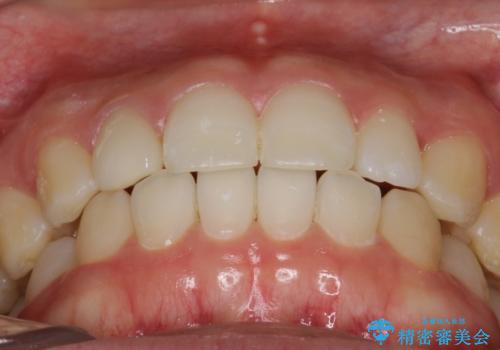

Invisalign インビザライン lite ライト 隙っ歯の改善

- マウスピース矯正による隙間の閉鎖を計画しました。

簡便な処置のため、ライトを選択しました。

かみ合わせが深くない空隙歯列は、最も簡単にその改善が見込まれます。